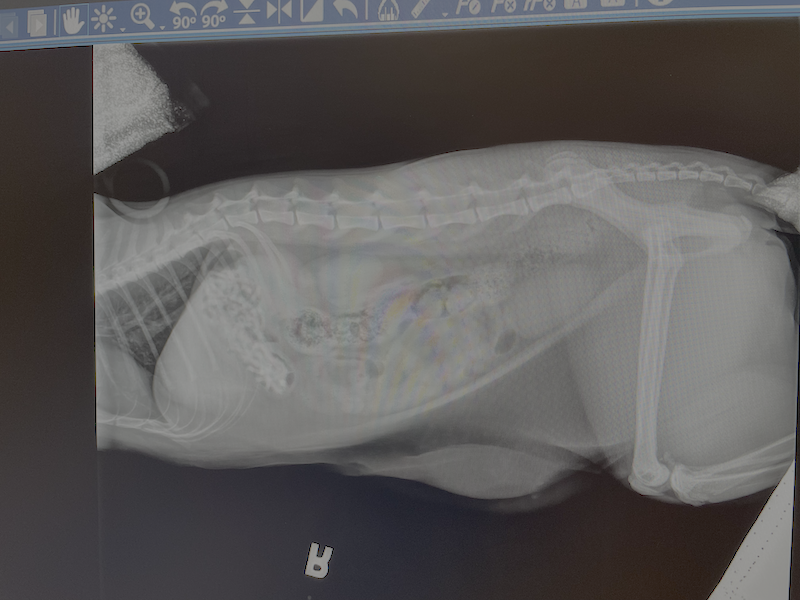

I write this from the veterinary hospital. My one-year-old cat Twiggy ate a dozen hair ties last night while we were at a friend’s house celebrating NYE. Alas, what an omen for 2026. I am almost certain that she’ll be ok. She’s always been our little diva, and now I have the vet bill to prove it.